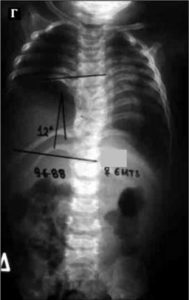

Ο πάσχων, 22 χρονών, λίγα χρόνια μετά τη γέννησή του, διαπιστώθηκε ότι παρουσιάζει ασυμμετρία του κορμού η οποία προοδευτικά επιδεινώνετο. Σε ηλικία περίπου 9 χρονών έγινε ακτινολογικός έλεγχος της Σπονδυλικής Στήλης (Σ.Σ.), κατά τον οποίο αποκαλύφθηκε σημαντικού μεγέθους σκολιωτικό κύρτωμα.

- α

- β

Εικόνα 1 (α,β,)

Παρατηρείται αριστερό Θωρακο-οσφυϊκό κύρτωμα μεγέθους 40ο περίπου μοιρών κατά Cobb επίσης δε ασυμμετρία και ανισοϋψία της πυέλου. Υπάρχουν πολλές συγγενείς ανωμαλίες των σπονδύλων (ημισπόνδυλοι σε όλη την έκταση της Σ.Σ., από τον αυχένα μέχρι το ιερό οστούν).